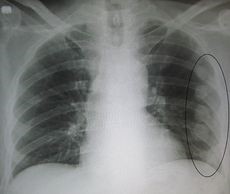

Ακόμη και όταν ο τραυματισμός μοιάζει ελαφρύς (ο θώρακας είναι κλειστός, δηλαδή δεν παρατηρείται εξωτερικό τραύμα), δεν αποκλείεται η περίπτωση ρήξης του ενός ή και των δύο πνευμόνων λόγω της πίεσης που ασκήθηκε από μία ή περισσότερες πλευρές. Γι’ αυτό τον λόγο είναι απαραίτητη η ακτινογραφία. Ένας άλλος κίνδυνος τον οποίο διατρέχει ο τραυματίας είναι, ως αντίδραση στον πόνο, να μειωθεί ο συνήθης όγκος εισπνεόμενου αέρα, με αποτέλεσμα να εκτεθεί σε ανεπαρκή πνευμονική κυκλοφορία.